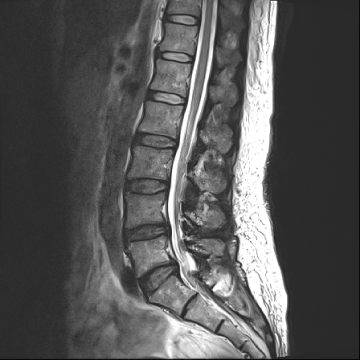

요추 협착증 수술 전·후

2020.08.30

2022.09.06

ㆍ환자 동의를 받은 자료이며, 이미지 사진은 실물과 다를 수 있습니다.

ㆍ모든 자료는 새움병원 자료입니다.